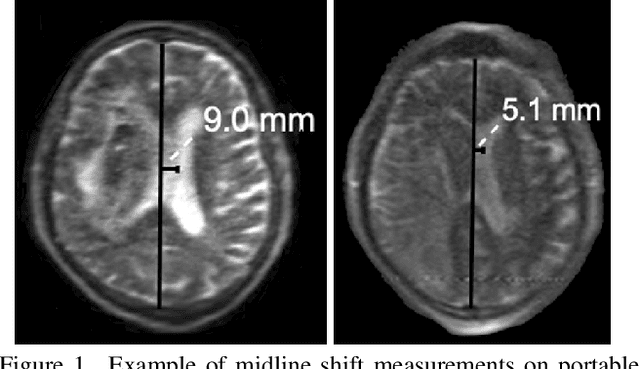

Abstract:Large Language Models (LLMs) are increasingly applied to medical imaging tasks, including image interpretation and synthetic image generation. However, these models often produce hallucinations, which are confident but incorrect outputs that can mislead clinical decisions. This study examines hallucinations in two directions: image to text, where LLMs generate reports from X-ray, CT, or MRI scans, and text to image, where models create medical images from clinical prompts. We analyze errors such as factual inconsistencies and anatomical inaccuracies, evaluating outputs using expert informed criteria across imaging modalities. Our findings reveal common patterns of hallucination in both interpretive and generative tasks, with implications for clinical reliability. We also discuss factors contributing to these failures, including model architecture and training data. By systematically studying both image understanding and generation, this work provides insights into improving the safety and trustworthiness of LLM driven medical imaging systems.